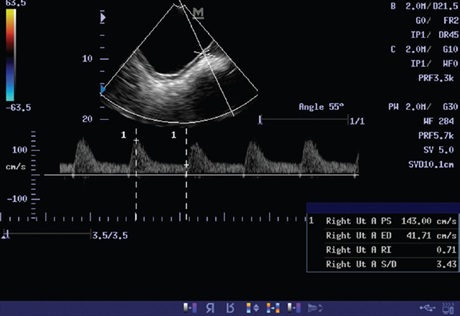

Materials and Methods: A total of 34 pregnant women with PIH at a gestational age of 24-37 weeks were prospectively examined with Doppler ultrasound of the fetal middle cerebral artery (MCA), umbilical artery and placental blood flow (uterine artery).

Results: The mean peak systolic velocity (PSV) of the fetal MCA was 8.23±3.96, resistance index (RI) was 0.763±0.07 and systolic diastolic (S/D) ratio was 4.558±1.36. The mean PSV of umbilical artery was 72.28±26.585, RI was 0.62±0.19 and S/D was 2.63±0.75. The mean placental blood flow (uterine artery) PSV was 141.34±70.58, RI was 0.59 and S/D was 2.42±1.07. Uterine artery PSV was normal in only six patients. Uterine artery was also not sonographically demonstrated in two patients.